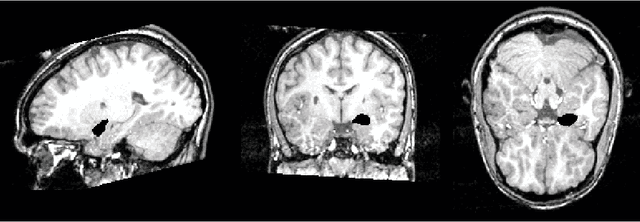

This article is based on the first chapter of book Chung (2013), where brain and medical images are introduced. The most widely used brain imaging modalities are magnetic resonance images (MRI), functional-MRI (fMRI) and diffusion tensor images (DTI). A brief introduction to each imaging modality is explained. Further, we explain what kind of curve, volume and surface data that can be extracted from each modality.